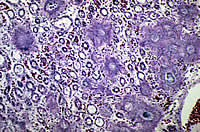

El sistema urinario de los Dálmatas trabaja en forma más parecida al del ser humano que al de los demás perros. Es decir: En vez de eliminar Urea en la orina como todos los perros, elimina Ácido Úrico como el ser Humano. Este Ácido Úrico es muy poco soluble en la orina y tiende a formar en la vejiga urinaria y en el riñón cristales de Uratos, lo que comúnmente llamamos Cálculos renales.

Otra medida importante y rutinaria en esta raza es el hacerles constantemente exámenes de orina para comprobar que no haya la presencia de cristales de Urato.